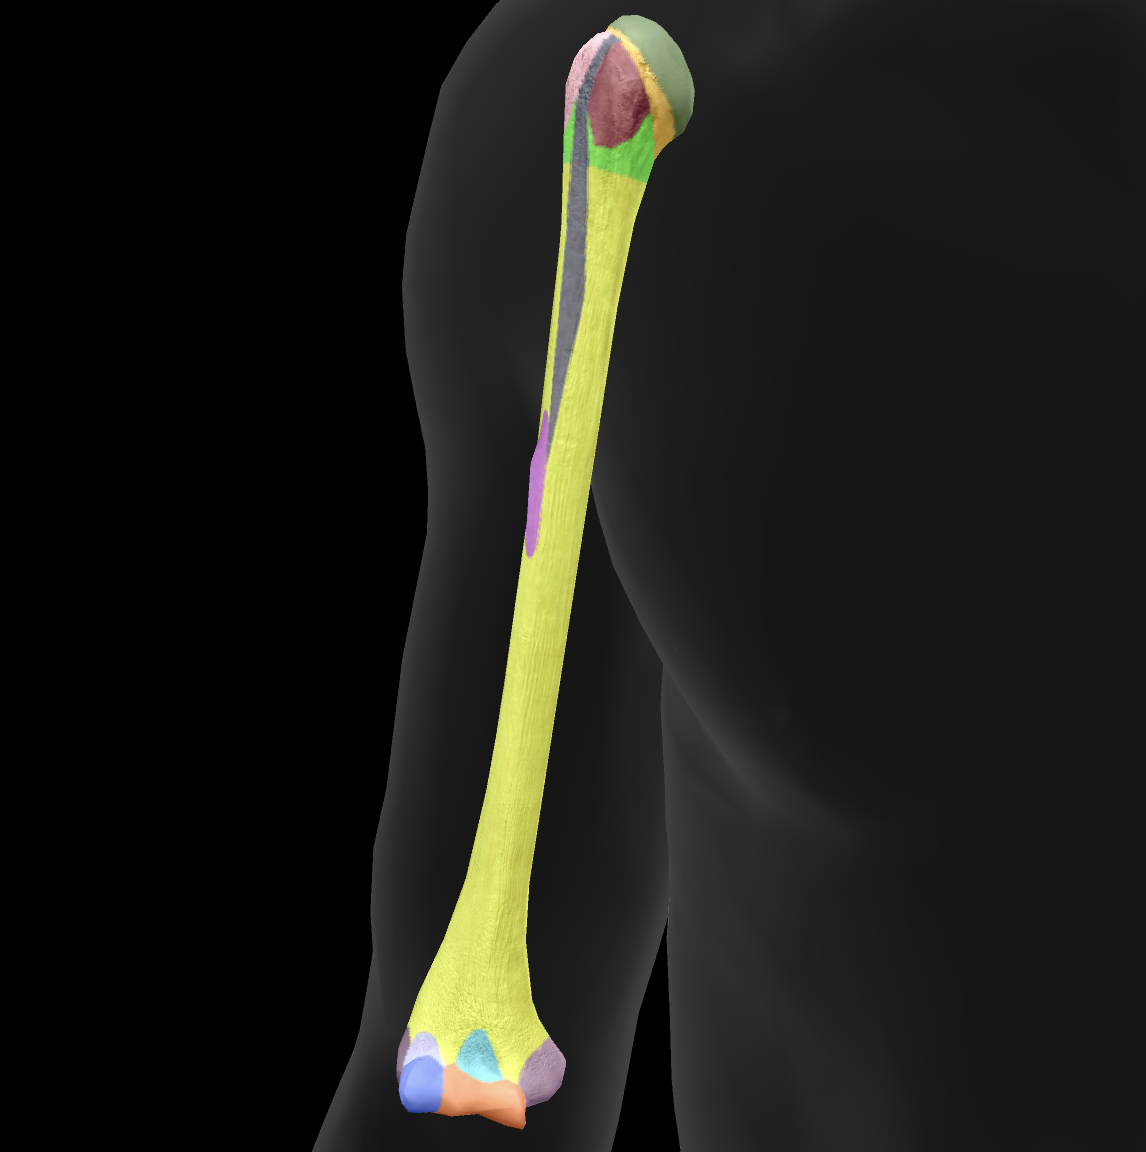

What bone is this?

humerus

What is this boney landmark?

head

What is this boney landmark?

anatomical neck

What is this boney landmark?

surgical neck

What is this boney landmark?

lesser tubercle

What is this boney landmark?

bicipital grove

What is this boney landmark?

deltoid tuberosity

What is this boney landmark?

shaft

What is this boney landmark?

capitulum

What is this boney landmark?

trochlea

What is this boney landmark?

radial fossa

What is this boney landmark?

coronoid fossa

What is this boney landmark?

medial epicondyle

What is this boney landmark?

lateral epicondyle

What is this boney landmark?

greater tubercle

What is this boney landmark?

radial grove

What is this boney landmark?

olecranon fossa

What is this boney landmark?

lateral supracondylar ridge

What is this boney landmark?

medial supracondylar ridge